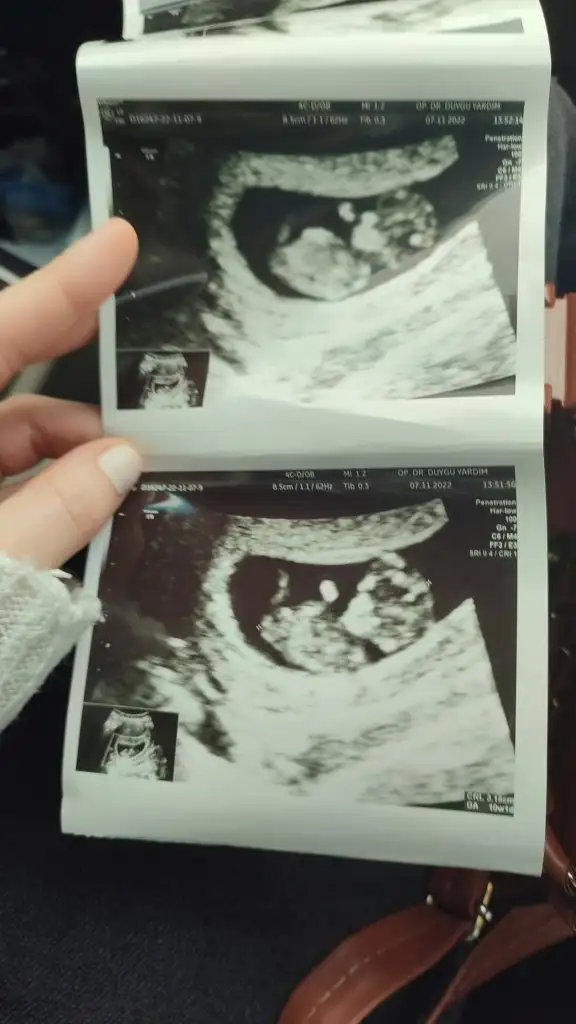

Bende 11+2 deyim doktorum tahminde bulundu ve erkek dedi ama ben hiç erkek hissetmiyorum bu zamana kadar sivilce çıkmayan yüzümde alnımda 4 tane sivilce çıktı ultrason fotoğrafını bırakıyorum Kızlar bana da bir tahmin de bulunsanız

• 97F69A29-0172-48F5-804F-C89DFF864AFC.webp

97F69A29-0172-48F5-804F-C89DFF864AFC.webp

38,2 KB · Görüntüleme: 153

• 2671E8B1-D719-41CB-9926-A47DE28FE885.webp

2671E8B1-D719-41CB-9926-A47DE28FE885.webp

36 KB · Görüntüleme: 152

• DEA35BDC-AE8A-44D5-928A-4CE427A903E4.webp

DEA35BDC-AE8A-44D5-928A-4CE427A903E4.webp

31,3 KB · Görüntüleme: 152